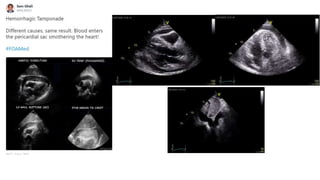

Constrictive pericarditis is a rare cause of obstructive shock.

Courtesy of Hatem Soliman